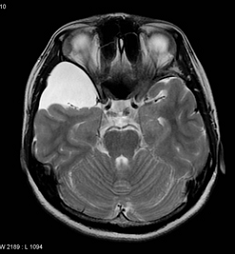

CEP TELEFONLARI KANSERE DAVETİYE Mİ ÇIKARIYOR?

Zaman zaman çoğu doktora cep telefonları beyin tümörüne sebep olurmu diyerek soruluyor. Bazıları öne ...

Küçük bir bebekten ileri yaştaki insanlara kadar herkeste görülebilen beyin tümörü en çok karşılaştı ...

Beyin tümörü kelimesinin gündeme gelmesi hem hasta hem de doktor açısından sıkıntılı bir durumun baş ...

Beyinde yerleşen tümörlerin çoğu kanser değildir, yani vücudun başka bir yerine atlamazlar, yani tıb ...